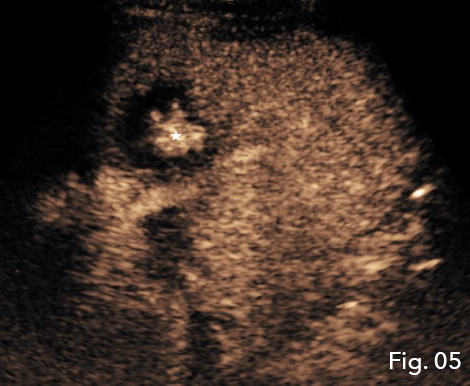

IV CEUS interrogation of the new second hypoechoic region superior to the primary abscess demonstrated features consistent with a hepatic abscess formation. IC CEUS demonstrated intracavitary communication between the two regions of abscess formation helping confirm the findings as a single abscess (Fig 4), negating the need for a second percutaneous hepatic drainage catheter. Furthermore the combination of IV and IC CEUS concluded that true fluid components were still present and the true size of the abscess cavity was much smaller than B-mode ultrasound had suggested (Fig 5).

Fig 5: IV and IC CEUS concluded the true fluid components were still present and the true size of the abscess cavity was much smaller than B-mode ultrasound suggested (star).